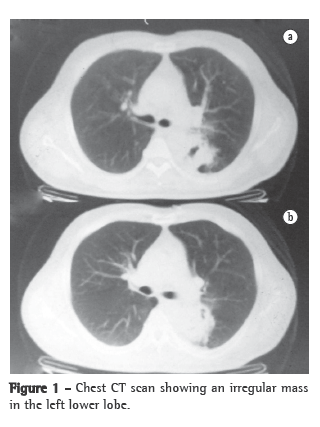

He was initially evaluated as a cardiology patient, due to suspected acute coronary syndrome, which was ruled out through electrocardiography, echocardiography and testing for cardiac enzymes. Therefore, the differential diagnoses were considered. The blood workup showed few eosinophils (2%; 130 cells). A chest X-ray and CT scan of the chest revealed an irregular mass in the upper segment of the left lower lobe, involving the left main bronchus, without involvement of the lymph nodes (Figure 1). Fiberoptic bronchoscopy with transbronchial biopsy revealed no alterations in the bronchial tree. The anatomopathological examination result was normal. Initially, we attempted to rule out TB and pulmonary mycoses. Tests for TB bacillus and fungi in the bronchoalveolar lavage (BAL) were negative, as was the BAL culture for TB and other bacteria. We then opted for thoracoscopy and biopsy. The histopathological examination of the material revealed the following: lung tissue with pronounced fibrosis and intense chronic inflammatory process; multiple granulomas with central areas of suppuration, containing numerous eosinophils; various multinucleated giant cells of foreign-body type and rare non-viable S. mansoni eggs; fibrin deposition; and areas of anthracosis/hemosiderosis (Figure 2).